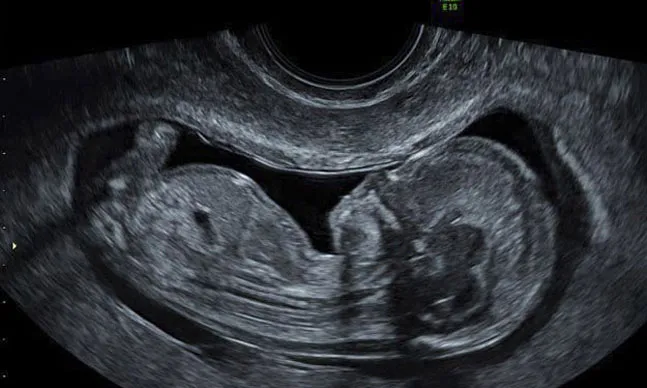

Ultrassonografia Morfológica

Nos preocupamos com a sua saúde e a do bebê, por isso realizamos este ultrassom que permite identificar precocemente a maioria das anomalias.

Ultrassonografia Obstétrica

Tenha acesso à avaliação do crescimento e desenvolvimento fetal, essencial para um acompanhamento pré-natal cuidadoso e preciso.